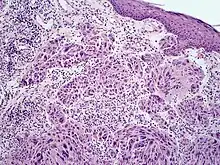

Melanoma with features of a Spitz nevus (also known as a "Spitzoid melanoma") is a cutaneous condition characterized histologically with tissue similar to a spitz nevus and with overall symmetry and a dermal nodule of epithelioid melanocytes that do not mature with progressively deeper dermal extension.[1]

Spitzoid melanoma in 10 year old